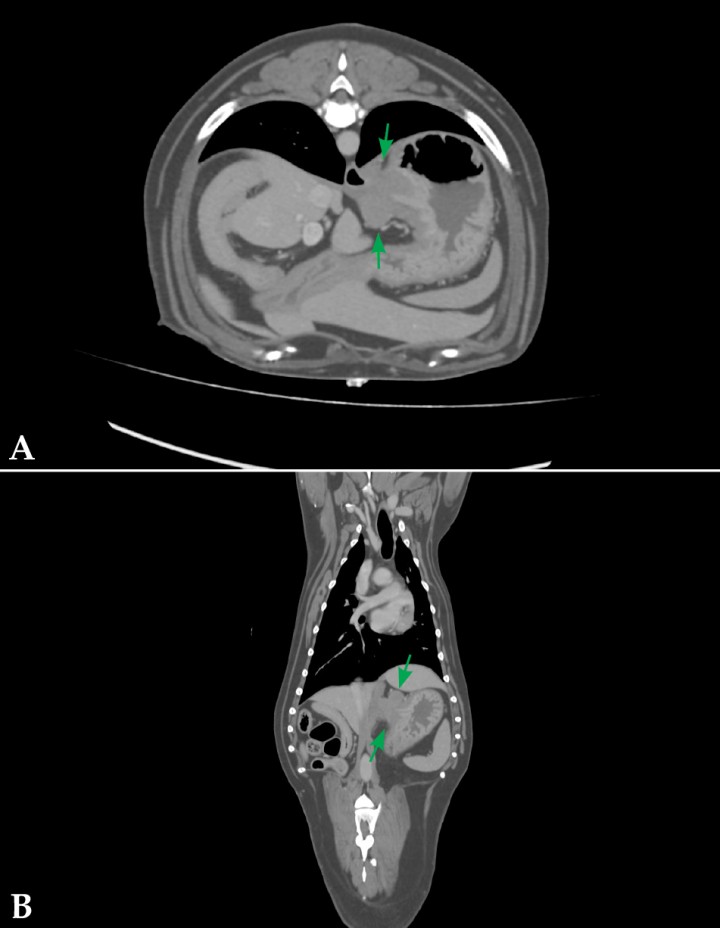

Dado el gran tamaño de la masa, se realizó una tomografía computarizada (TC) con el objetivo de evaluar los límites de la lesión y descartar la posible invasión de la cavidad abdominal. Se realizó una valoración preanestésica previa a la TC que incluyó como pruebas complementarias un hemograma y perfil bioquímico completos, donde no se observaron alteraciones reseñables. Los hallazgos observados tras la TC fueron compatibles con un lipoma infiltrativo (11,5 cm de largo, por 8 cm de ancho y 4,5 cm de altura) que se extendía desde el área de proyección de T12 hasta L6, entre los músculos oblicuo interno y transverso del abdomen (Fig. 1). En el mismo estudio se observaron, de forma accidental, una neoplasia gástrica (Fig. 2) y una lesión hepática, de aspecto quístico y 2,8 cm de diámetro en el lóbulo medial izquierdo. Dados los resultados obtenidos, se amplió el estudio de TC a la región torácica donde no se observaron alteraciones reseñables. Se realizaron citologías de las lesiones hepática y gástrica en las que se obtuvo un resultado compatible con hiperplasia nodular para la lesión en hígado y con leiomioma como diagnóstico más probable en estómago. Se planteó la resección quirúrgica de las lesiones localizadas en pared abdominal y estómago y la toma de biopsias de la lesión hepática. El paciente fue clasificado como ASA III en el momento de la TC y cirugía.

<p>Imagen postcontraste axial (<strong>A</strong>) y dorsal (<strong>B</strong>) de TC, en ventana tejido blando, donde se observa una masa excéntrica (flechas), bien delimitada, que parte de la capa muscular del estómago, caudal y medial al cardias.</p>

Figura 2

Imagen postcontraste axial (A) y dorsal (B) de TC, en ventana tejido blando, donde se observa una masa excéntrica (flechas), bien delimitada, que parte de la capa muscular del estómago, caudal y medial al cardias.